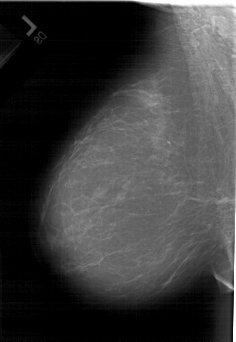

A_1440_1.LEFT_MLO

LEFT_MLO LINES 6481 PIXELS_PER_LINE 4471 BITS_PER_PIXEL 12 RESOLUTION 43.5 NON_OVERLAY